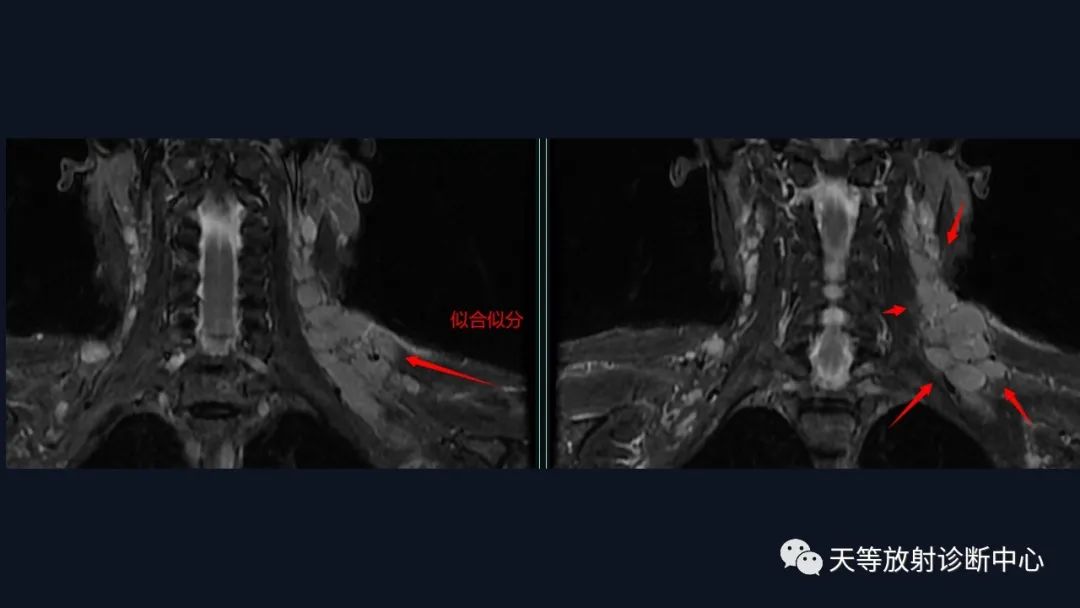

本病例影像学特点:

脑内占位的特点:

1、刀切征

2、凹陷征或肚脐凹征

3、尖角征

4、多发

5、DWI呈稍高信号

6、形态上怪异

6、NAA及Cho减低,出现导致LL峰。

结合颈部、胸廓入口区及腋窝多发淋巴结肿大并相互融合。

综合考虑淋巴瘤